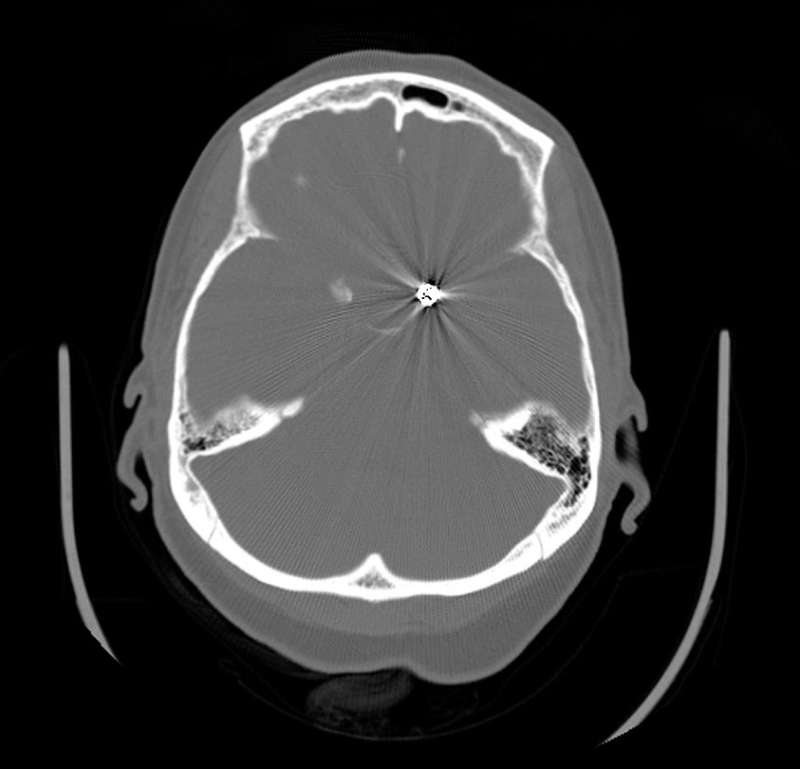

Endovascular treatment of irregular and complicated intracranial aneurysms with coils using

Endovascular treatment of irregular and complicated intracranial aneurysms with coils using Codman Aneurysm Coils Mri Safety special positioning of the codman microsensor is required to ensure patient safety during the mri procedure. codman neurovascular fill coils feature innovative technology designed to promote complete, homogeneous. in the clinical magnetic resonance imaging (mri) setting, it is often necessary to manage patients with embolization coils. Titanium alloy) have been tested and shown to be safe for. Codman Aneurysm Coils Mri Safety.